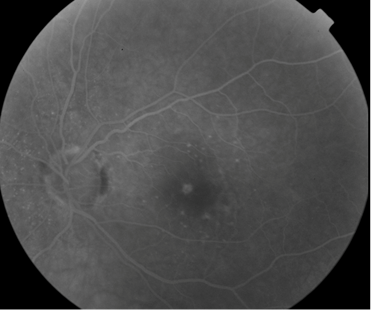

FUNDUS DESCRIPTION: |

OD OS |

OD Red-Free: Pre-Injection: Arterial: A-V: Venous: Recirculation: Late:

OS Red-Free: Venous: Recirc: Late:

Impression